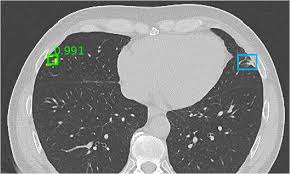

- Lung cancer detection and staging

- Nodule and lesion analysis

- Automated anomaly detection

- Intuitive visual highlights